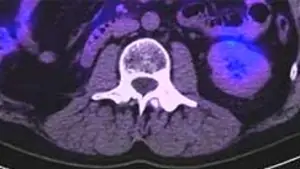

Лечение метастазов почечно-клеточного рака в позвоночном столбе кибер-ножом

Изображении ПЭТ-КТ с метастазом почечно-клеточного рака в позвоночном столбе

Через 6 месяцев после лечения Киберножом. Контрольный снимок показал отсутствие опухоли, в области прежнего поражения образовалась костная мозоль